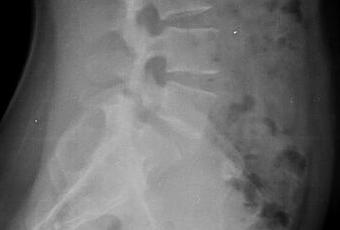

RADIOGRAFIA LATERAL DE COLUMNA LUMBAR

-Tejidos blandos, con densidad y morfología respetada, sin evidencia de lesiones.

-Sin listesis. Lordosis con adecuada angulación.

-Cuerpos vertebrales con altura preservada, sin evidencia de lesiones líticas, blásticas o perdida de la contigüidad.

-Existe imagen de perdida de la contigüidad a nivel de L5-S1 a nivel de facetas articulares. Resto de pedículos, laminas posteriores y facetas, sin evidencias de lesiones líticas, blásticas o perdidas de la contigüidad.

-Apófisis espinosas y transversas sin evidencias de lesiones líticas, blásticas o perdidas de la contigüidad.

-Espacios intervertebrales con amplitud respetada, sin evidencia de alteraciones.

-Forámenes de L5-S1, con aparente disminución de su amplitud, resto sin alteraciones..

OPINIÓN RADIOLÓGICA:

EL PRESENTE ESTUDIO RADIOGRAFICO, EXISTE ESPONDILOLISIS DE L5-S1.

APARENTE ESTENOSIS DE NEURO FORAMEN DE L5-S1.

RESTO SIN ALTERACIONES SIGNIFICATIVAS.

CORRELACIONAR CON DATOS E HISTORIA CLINICA DEL PACIENTE